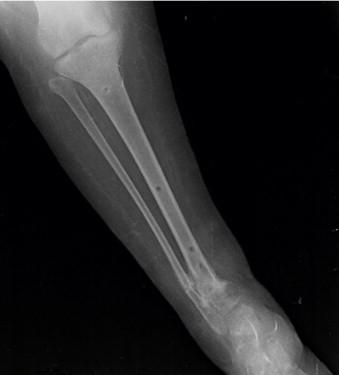

Serratia marcescens is an unexpected pathogen for subacute osteomyelitis in adolescence. Because of difficulty of diagnosis, treatment can be delayed or cause complications like nonunion or loss of function. We present a meningomyelocele female adolescent operated with distal tibia varus osteotomy for correcting ankle valgus deformity. Insufficient healing was determined at osteotomy side on radiographs. The patient's erythrocyte sedimentation rate and CRP level was slightly higher with minimal clinical inflammation. MRI examination showed abscess formation at T2 imaging. Debridement, grafting and circular external fixation was performed. Sulperazon was started for drug therapy. Union was achieved after compression and distraction osteogenesis by circular external fixator. Orthopedic surgeons should be aware of opportunistic infections like serratia and keep in mind as a probable cause of disease.

粘质沙雷氏菌是青少年亚急性骨髓炎中一种意想不到的病原体。由于诊断困难,治疗可能会延迟或导致诸如骨不连或功能丧失等并发症。我们报告一名患有脊髓脊膜膨出的女性青少年,她接受了胫骨远端内翻截骨术以纠正踝外翻畸形。X线片显示截骨部位愈合不佳。患者的红细胞沉降率和CRP水平略有升高,临床炎症轻微。MRI检查在T2成像上显示有脓肿形成。进行了清创、植骨和环形外固定。开始使用舒普深进行药物治疗。通过环形外固定器进行加压和牵张成骨后实现了骨愈合。骨科医生应意识到像粘质沙雷氏菌这样的机会性感染,并将其作为可能的病因牢记在心。